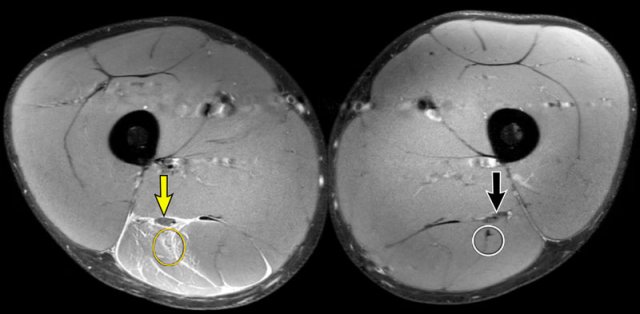

Based on coronal images alone, it is sometimes challenging to exactly classify the amount of distortion. Use the axial images to get a closer look.

On these axial images, high signal and thickening of the left biceps femoris tendon (yellow dotted circle) is seen when compared to the non-injured side (white dotted circle).